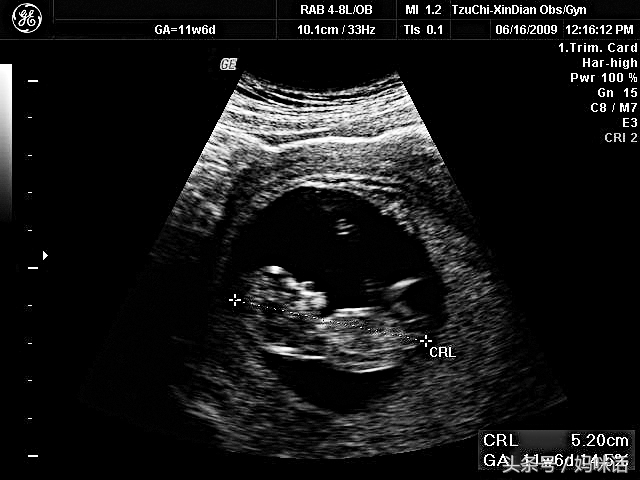

图这张应该是大家最看得懂的照片了,大约是怀孕三个月左右时拍的。片中5.20公分的是头臀长(crown-rump length, CRL),对照的周数是11周又6天。CRL在怀孕早期(四个月前)是评估胎儿生长发育最重要的指标。

好多孕妇曾经问我:「医生,我看妈妈手册上面写着,今天宝宝的身长应该有18公分了,为什么你只量11公分啊?」现在,妳知道答案了吗?我们量测的是头臀长,并非头脚底长,难怪会短了一大截。